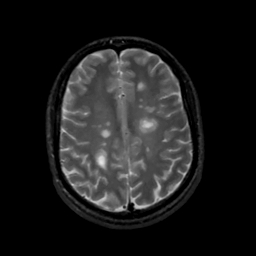

MR Study #10, April 28, 1991 -- Slice #35

[Home][Help][Clinical][Tour 1][Tour 2] Slice 35